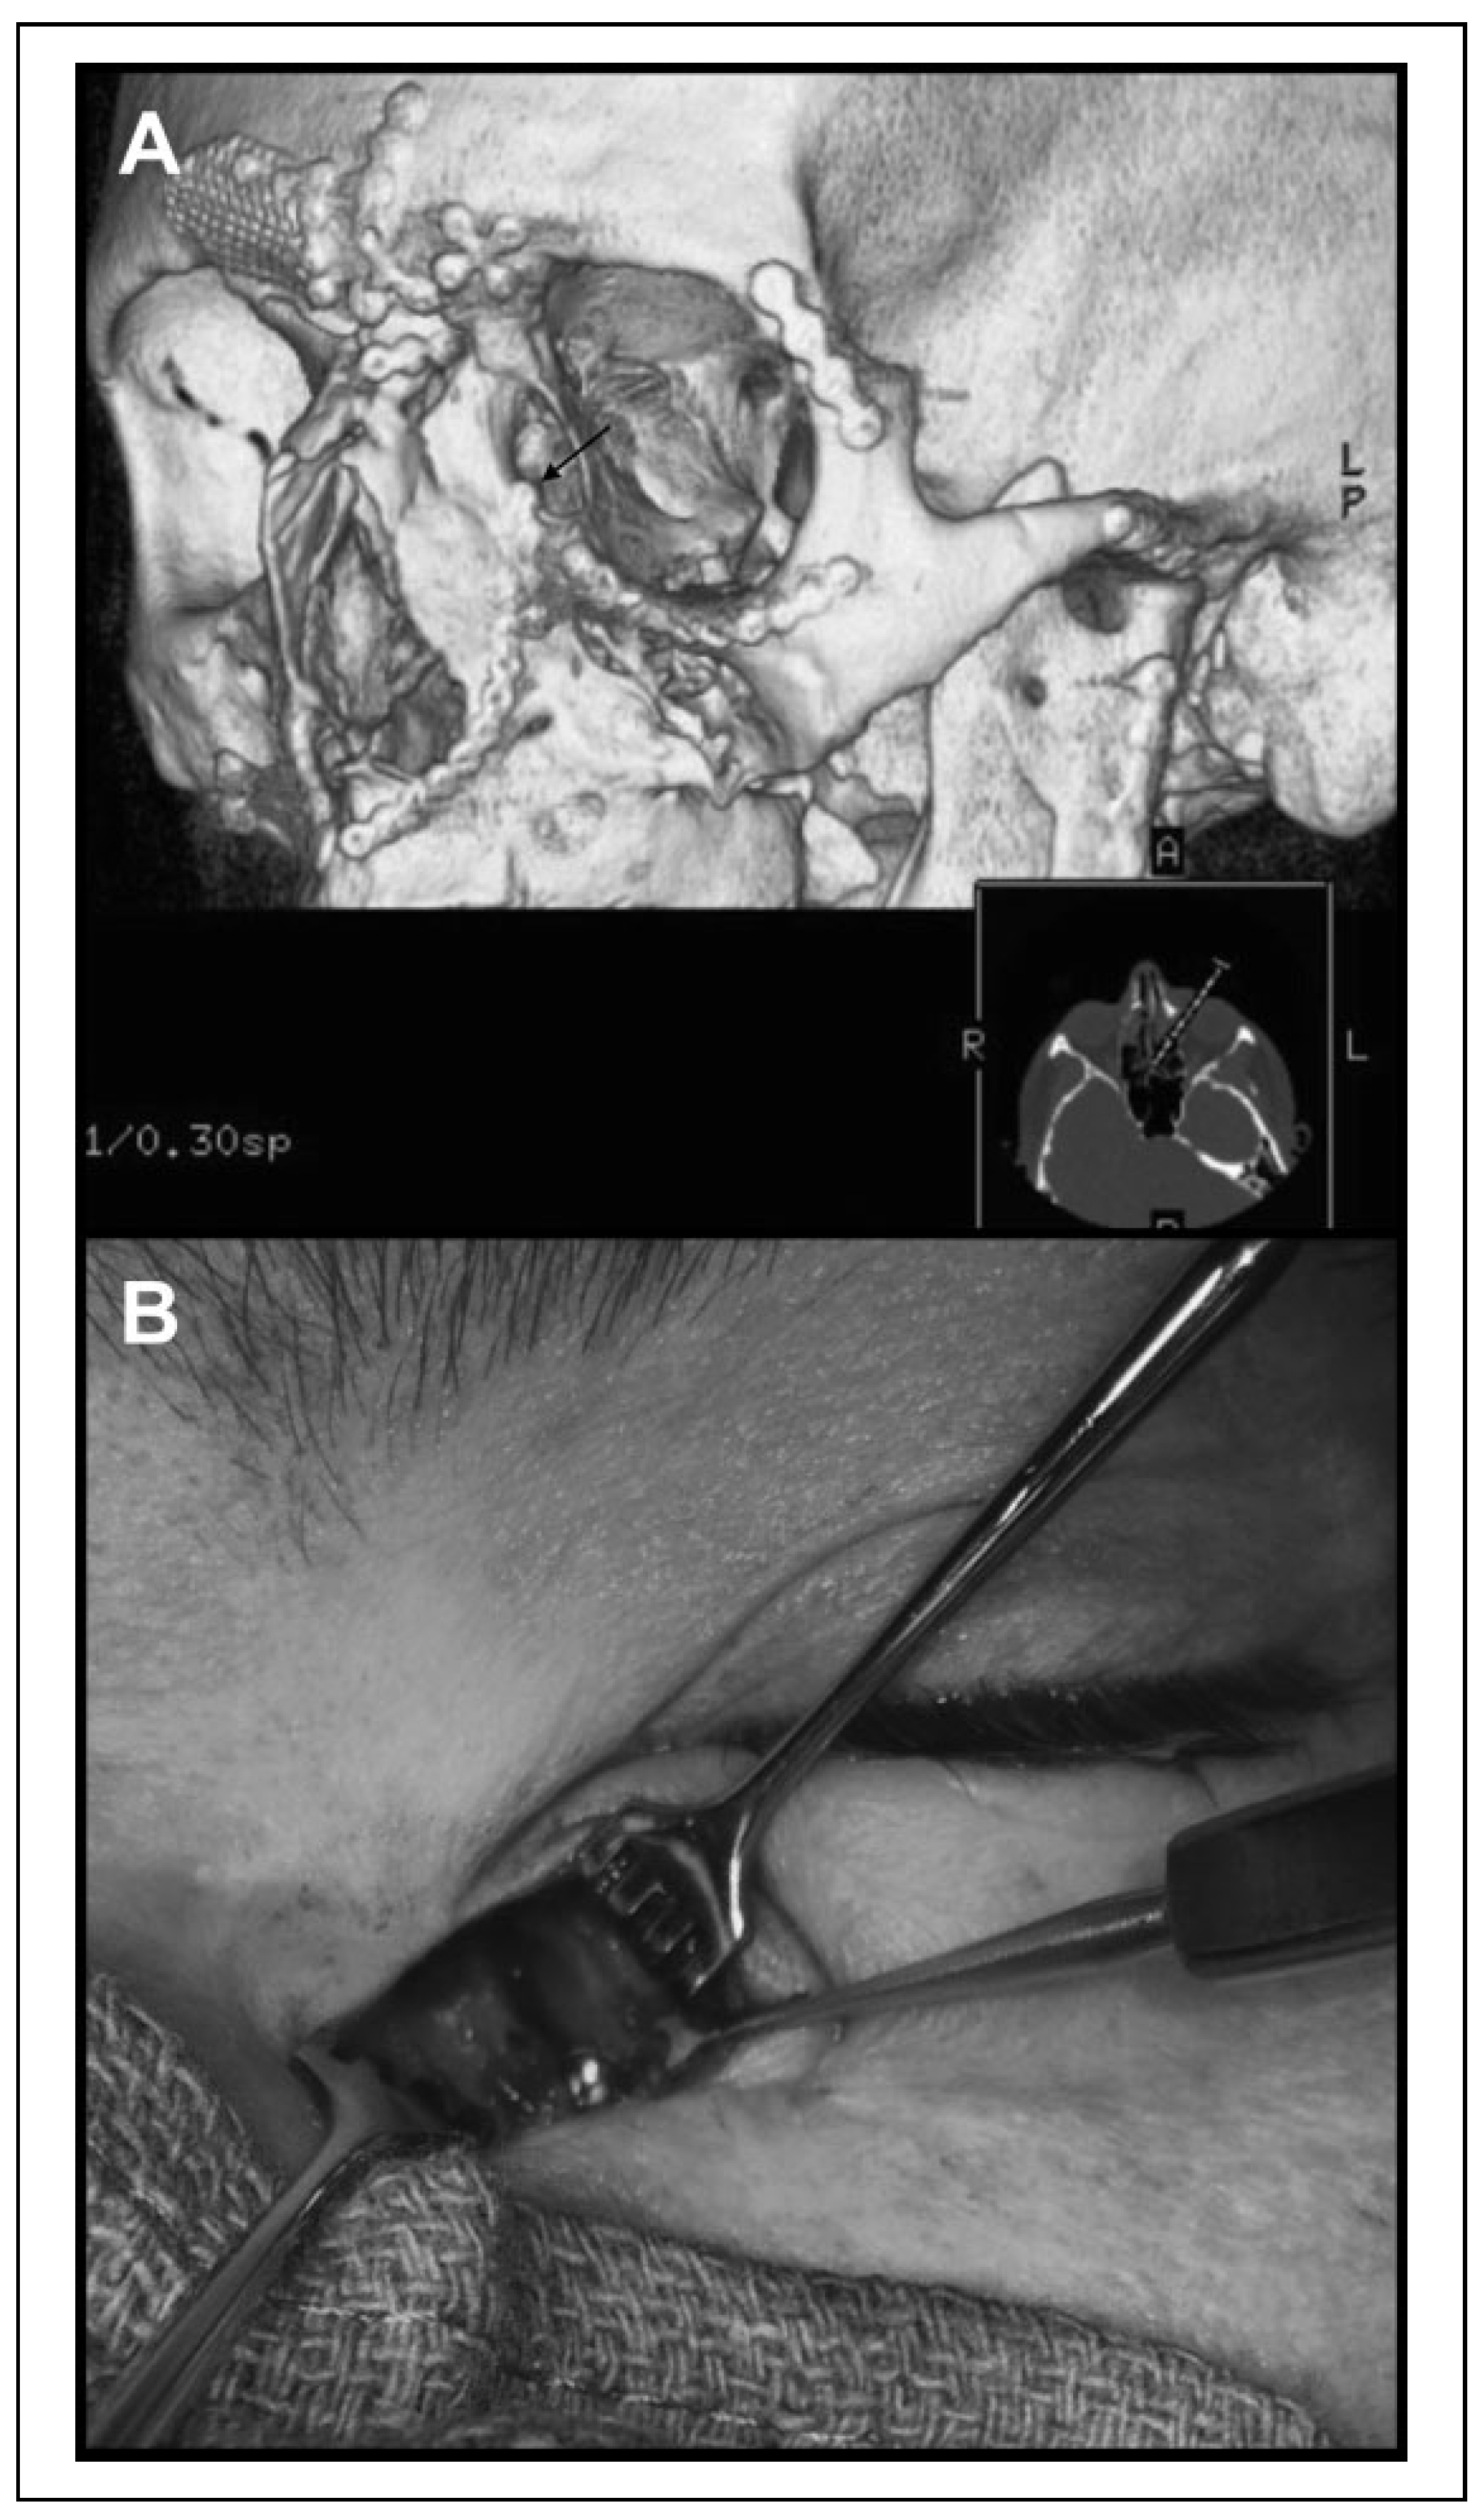

Figure 2. Case 4: Volume rendering of the CT orbit (A) shows a screw (black arrow) going through the lacrimal sac fossa. An image taking intraoperatively (B) also demonstrates the screw entering the lacrimal sac fossa. CT indicates computed tomography.

Case 4: A 29-year-old man presented with left-sided epiphora. The patient reported left-sided facial trauma 2 years prior that required reconstructive surgery. Operative reports from the prior surgeries were unavailable. On imaging, microplate fixation screws through a linear titanium implant appeared to enter the left lacrimal sac fossa (Figure 2A).

We performed an external DCR, during which screws were found to be placed through the frontal process of maxilla into the lacrimal sac fossa (Figure 2B). The titanium plate and screws were explanted and an external DCR was performed. The patient was epiphora-free 3 months postoperatively with 100% patent lacrimal system irrigation.